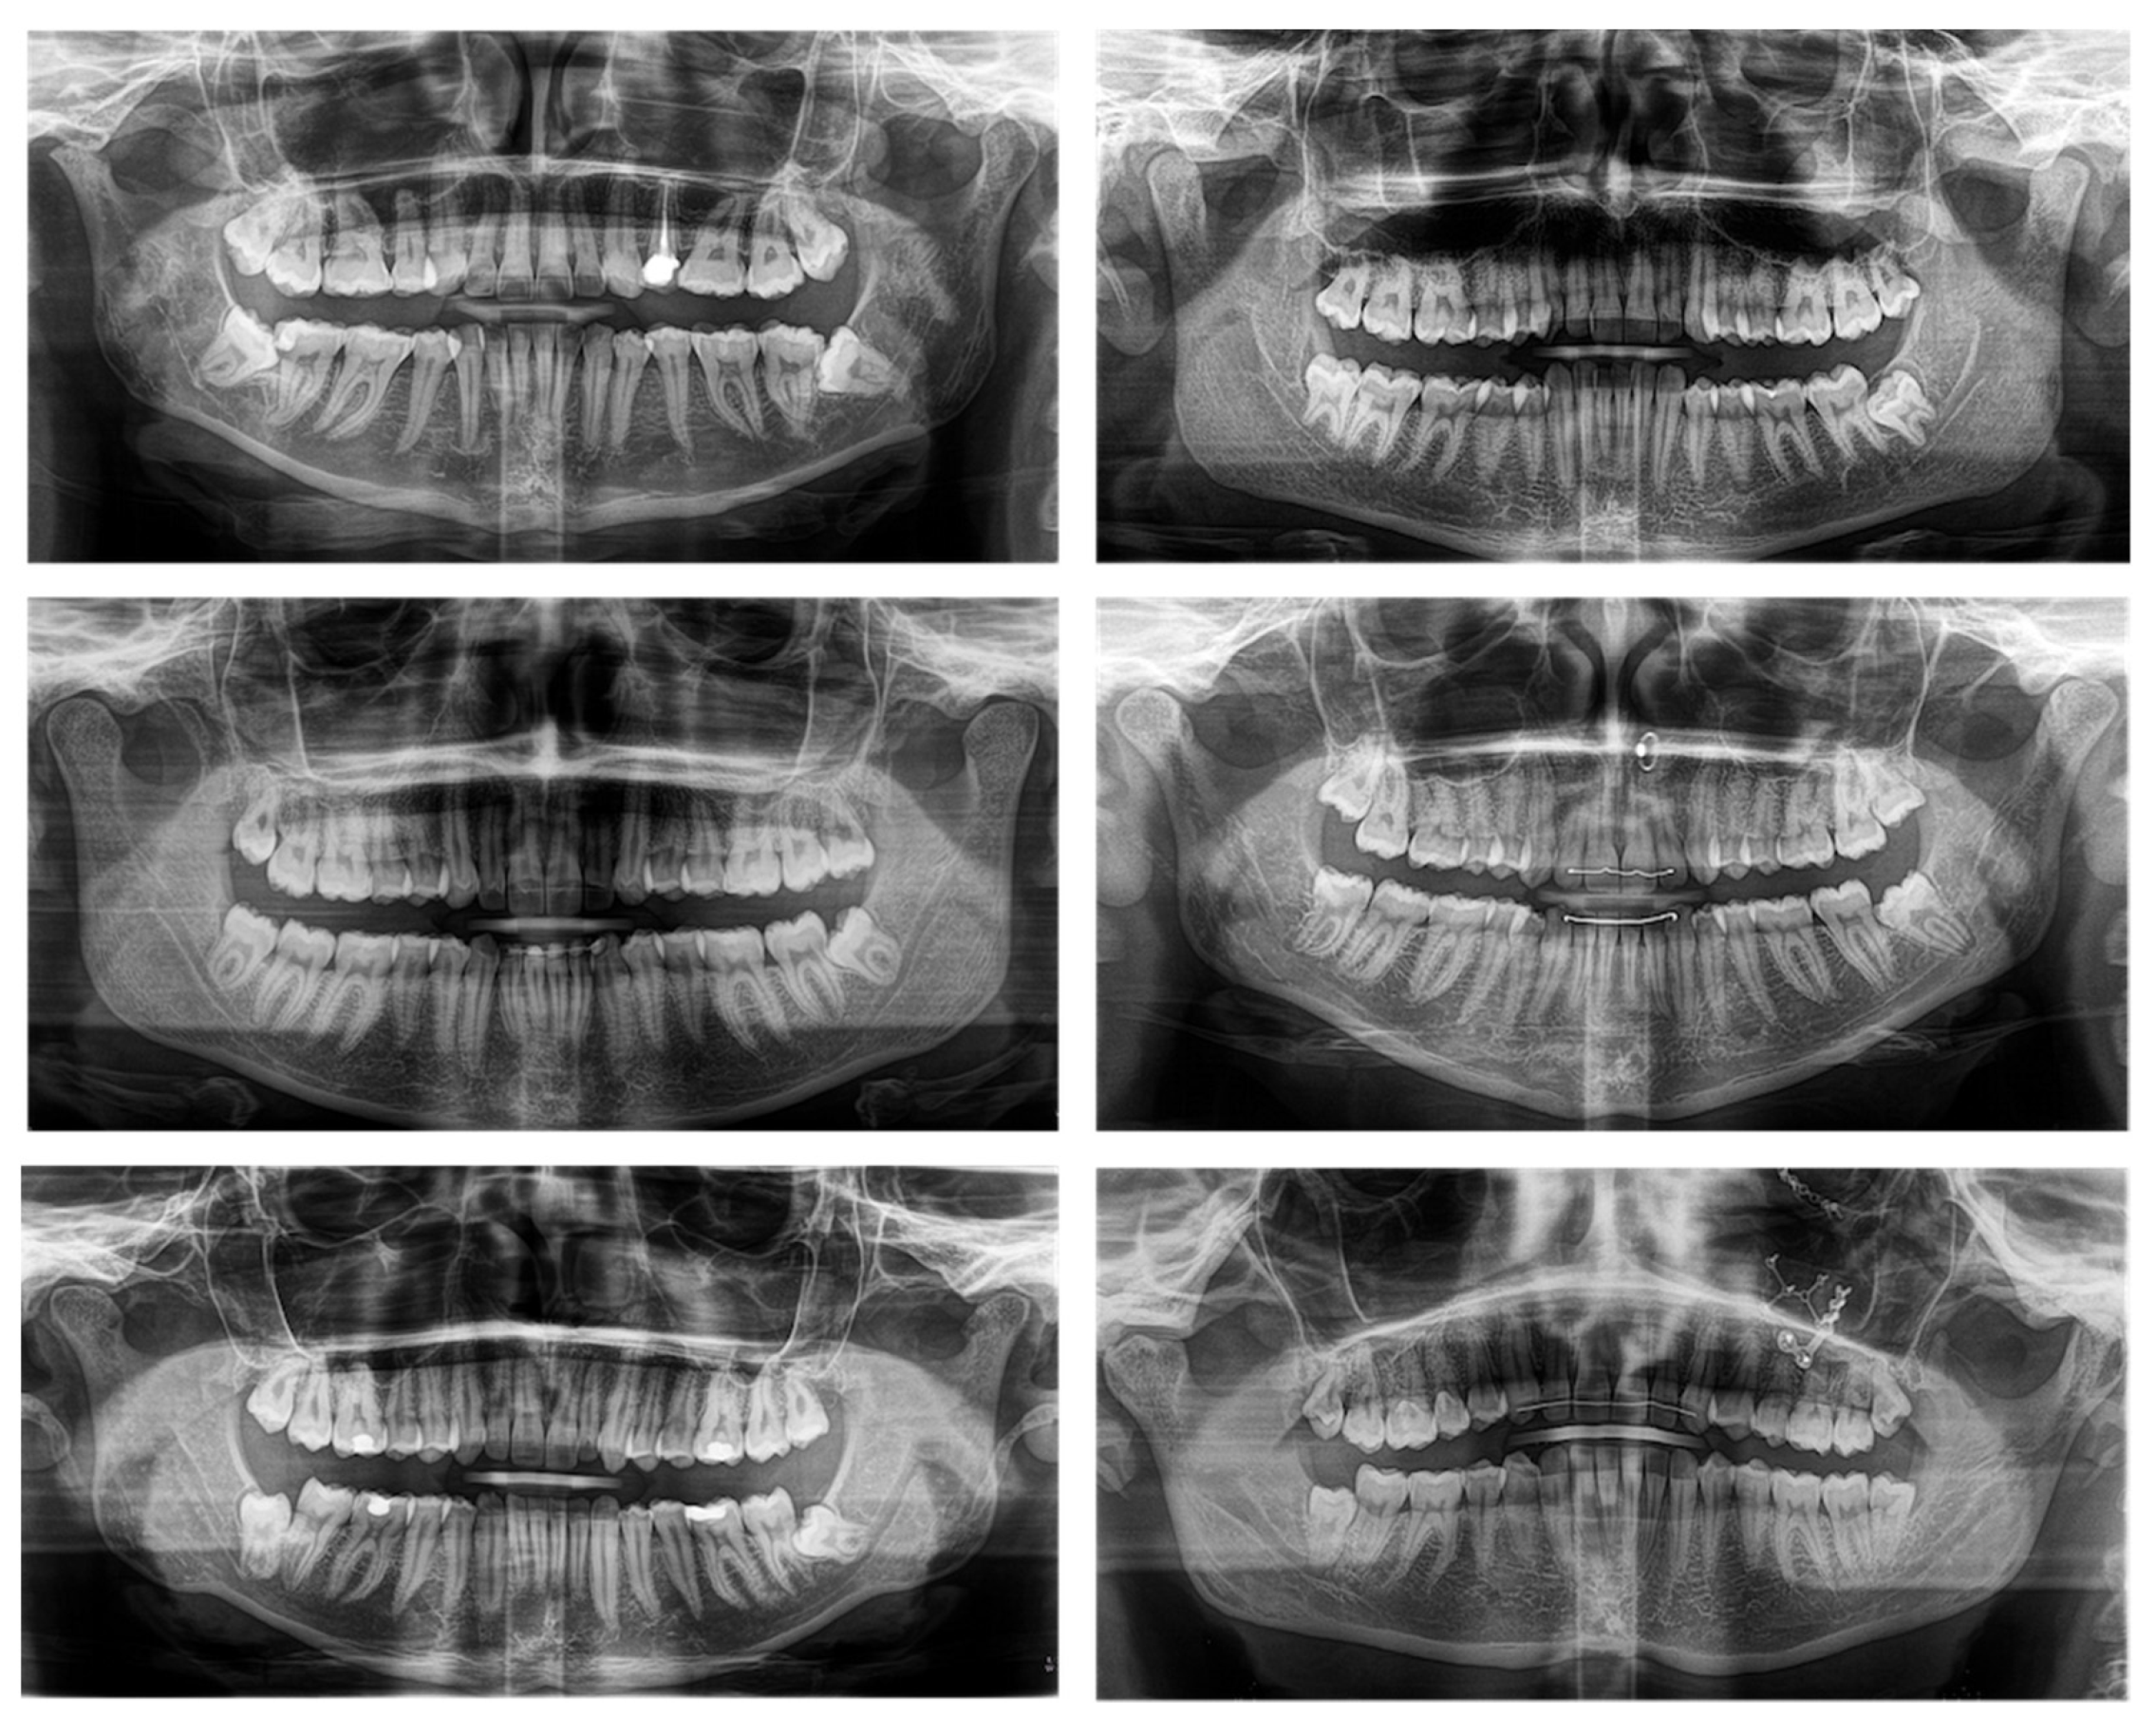

Figure 1. Study participants’ two-dimensional panoramic radiography (PAN) providing anatomical information about the angulation and position of the mandibular third molars (MTM) and the spatial proximity between the roots of the MTMs and the mandibular canal (MC). All participants showed an indication for the removal of MTMs and a close relationship between the MC and the MTM; therefore, these were considered high-risk cases and show indication for three-dimensional imaging.

The estimated number to be enrolled in 8 months was 20, whereby the study participants’ recruitment took place between May 2018 and December 2018, with an indication for the removal of MTMs, showing a close positional relationship between the IAN/MC and the roots of the MTMs in PAN indicating three-dimensional imaging according to the guidelines of the Swiss association of dentomaxillofacial radiology and therefore considered as high-risk cases [6] (Figure 1).